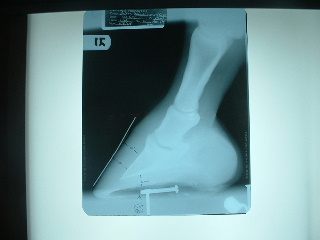

He's ouchy on the left front and very stiff in his hind end; vet came out yesterday and took xrays of his feet knowing that shoes will be put on.

He's been on weekly adequan for the last 4 weeks and he seemed to get worse... his right hind was shaking last week when I went to clean his foot. Vet thinks it may be because he only has 11mm of sole depth. He didn't block him, but did examine and watch him move and examined him again. No soft tissue issues, but very sensitive to hoof testers along the bars and the bulb of his heels. I did tell him that my farrier has not been working due to injury, so he's at 5 weeks now without a trim.

I'm afraid being barefoot is actually exacerbating his hind end arthritis and the vet said it's possible because he's loading the hind more to take weight off the front. I asked the vet if he thought I made a mistake by taking him barefoot and he said no. His hoof form is wonderful and to get to that with shoes would have taken MUCH longer. He does not believe navicular is an issue any longer as long as his hoof form stays correct.

The good news: we've fixed the front feet, he believes that putting on Epona shoes on the front will help a lot and that I will be able to ride/show him this year.

I think he looks really good but he's telling us something different. On the xrays, you'll see a nail on the bottom, the tip of the nail is the tip of his frog. Vet said the toe could come way back:

Left front:

Right front:

They look good Aileen and especially have improved a bit in the run under heels, a difficult and slow correction to be sure. I do not see a lot of room to back the toe further in the images though break over could be moved back a touch. I might feel different after actually examining the feet.